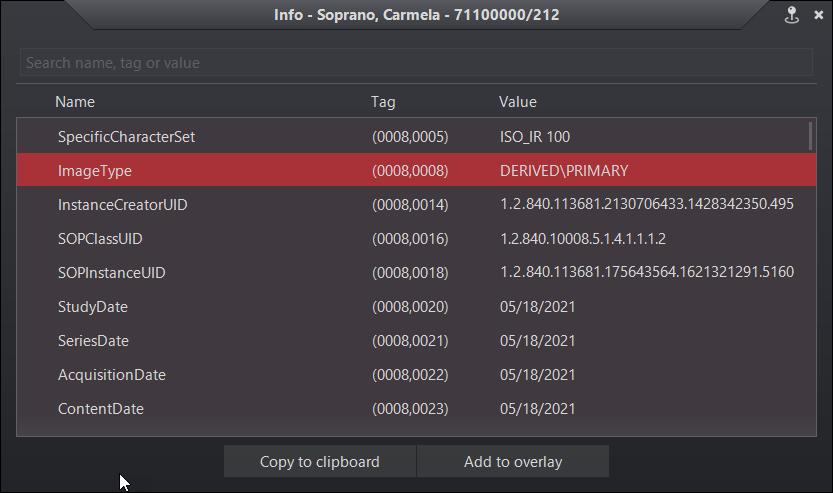

Update the DICOM info panel

The DICOM information panel has been updated to conform to the Evo viewer’s look and feel. The panel contains search functionality, copy to clipboard, and an add overlay option.